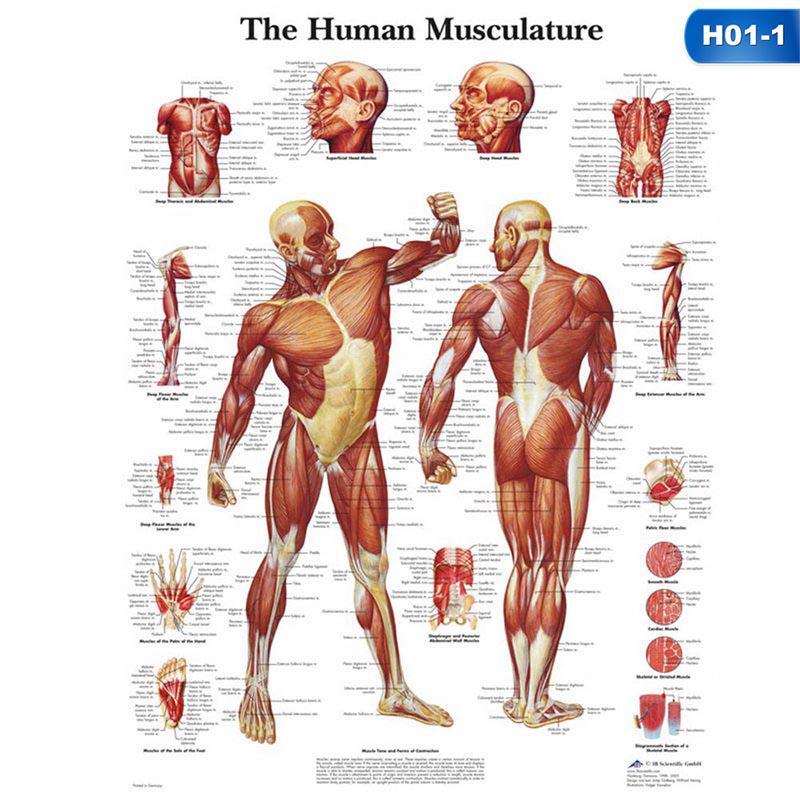

Свойства мышц человека: Основные характеристики

Раздел: Объективный взгляд